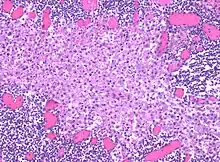

Sinus histiocytosis, a common feature in lymph node biopsies, is characterized by dilated sinuses containing variable numbers of histiocytes.[5]